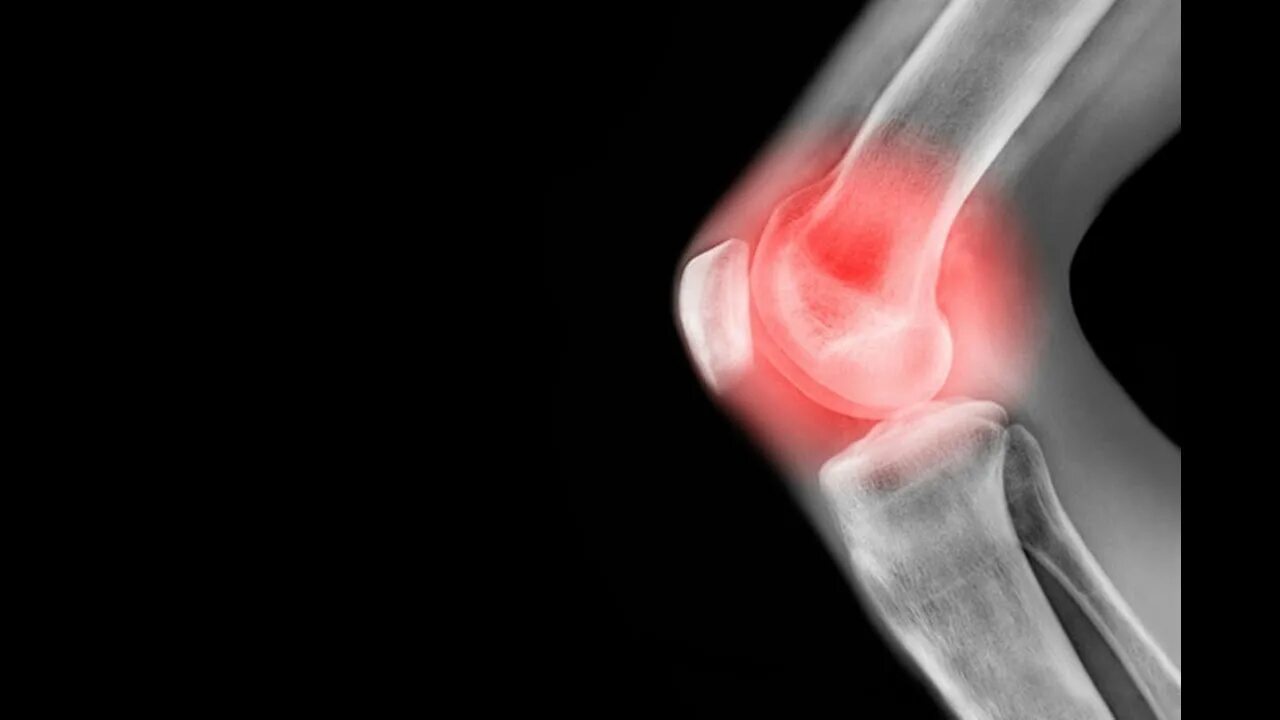

Пульсирующие боли в суставах